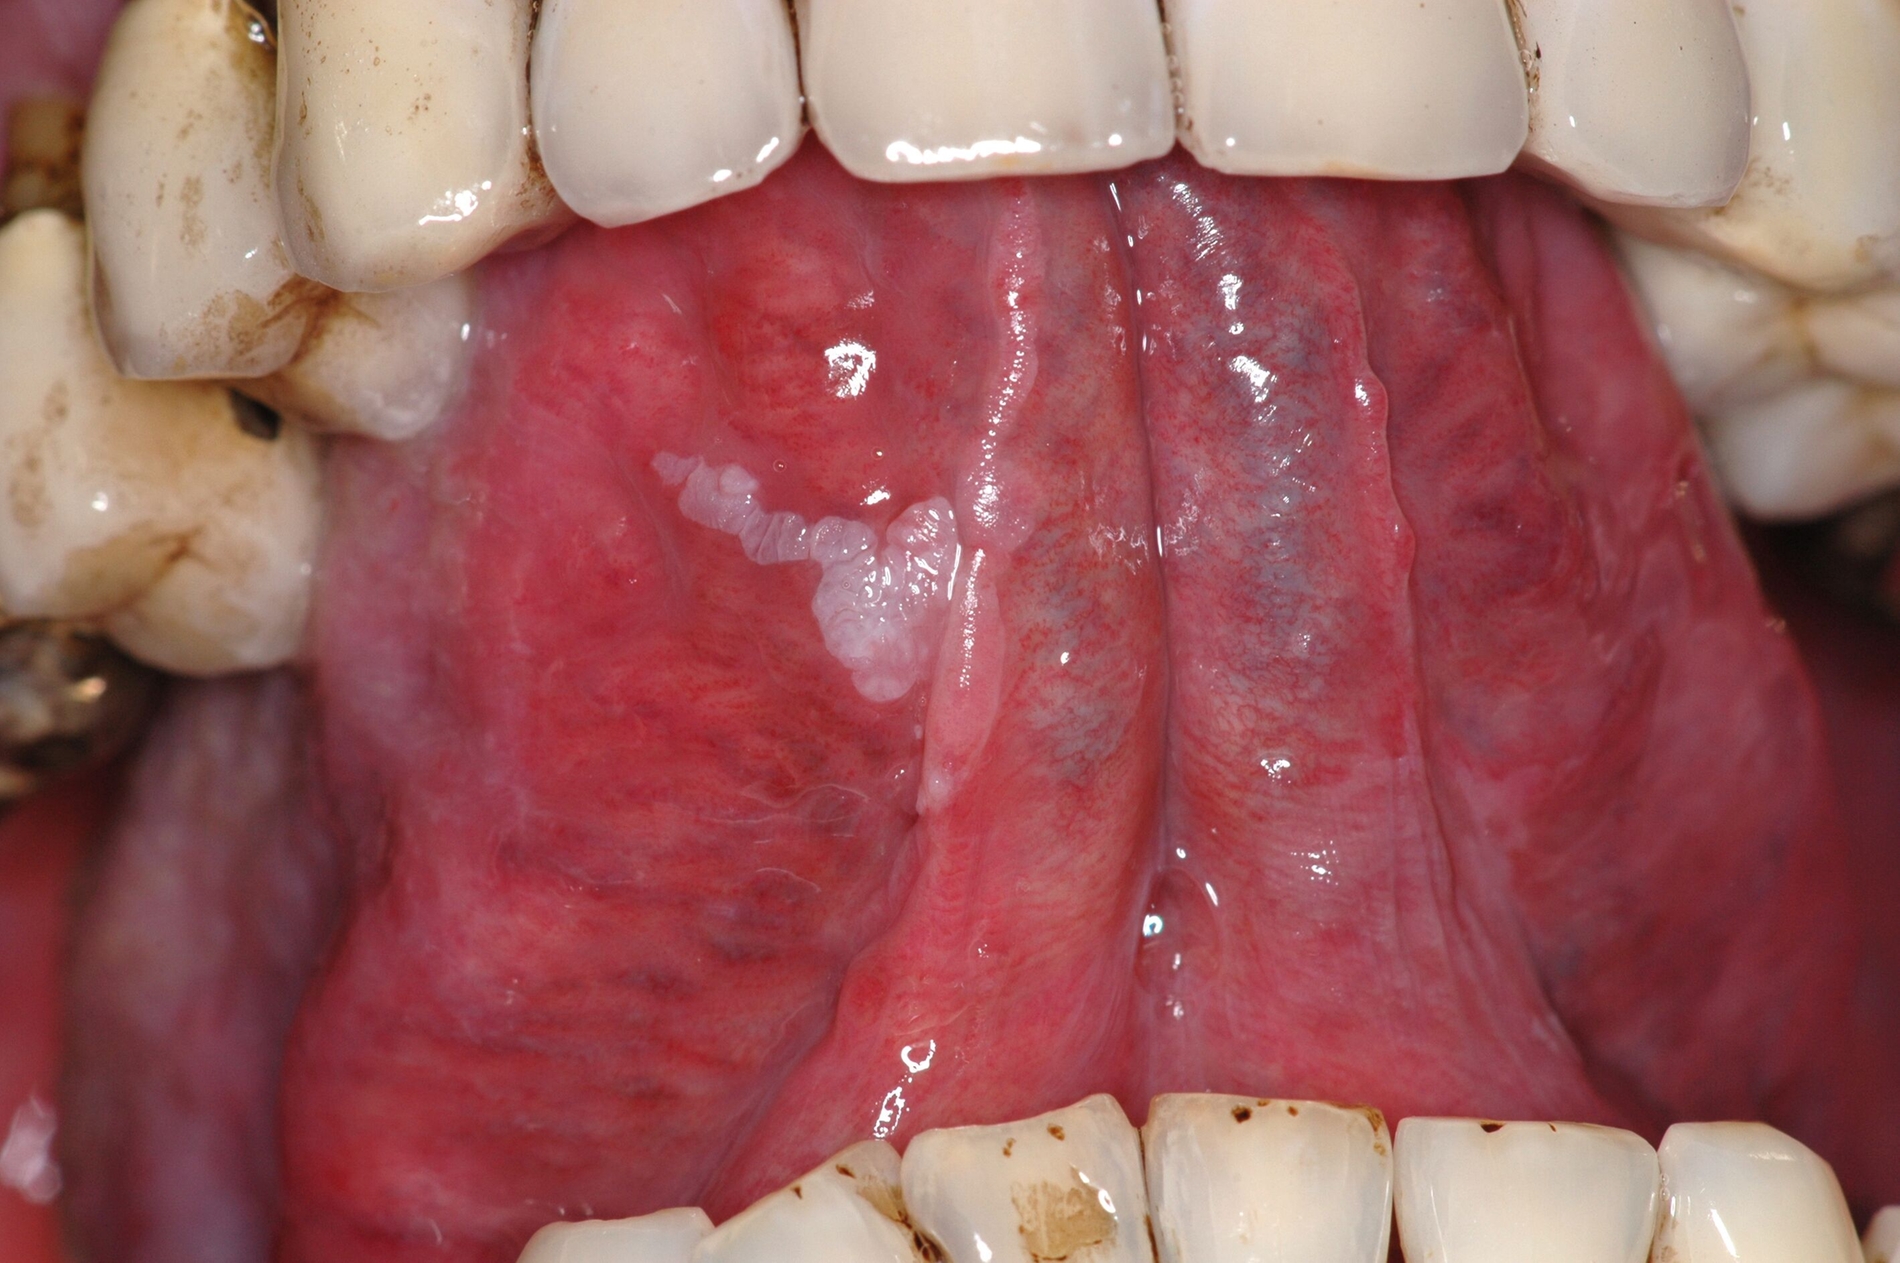

Das Problem: Die geschätzte Zahl der Neuerkrankungen bei Tumoren der Mundhöhle und des Rachenraums lag – nach den aktuellsten Zahlen des Robert-Koch-Instituts (RKI) – im Jahr 2018 bei über 14.000 Fällen deutschlandweit. Davon waren 9.820 Männer und 4.490 Frauen betroffen. Gemessen an der Zahl aller Krebserkrankungen waren dies bei Männern 3,7 Prozent – Tumoren der Mundhöhle nehmen damit bei den Neuerkrankungen die achte Position bei den Männern ein. Bei den Frauen war es mit 1,9 Prozent die 13. Stelle. Die Fünf-Jahres-Überlebensrate in Deutschland lag bei Männern bei nur 52, bei Frauen bei nur 62 Prozent.

Die Relevanz des Projekts liegt nach Angaben der Forschenden auf der Hand: Obwohl sich die Behandlungsstandards in Diagnostik und Therapie in den vergangenen Jahrzehnten kontinuierlich verbessert hätten, habe sich dies nicht merklich positiv auf die Absenkung der Mortalitätsrate ausgewirkt. Als Grund geben die Forschenden an, dass sich mehr als die Hälfte der Betroffenen erst in einem fortgeschrittenen Stadium an einen Zahnarzt, einen Mund-, Kiefer- und Gesichtschirurgen oder eine ärztliche Fachdisziplin (zum Beispiel Hals-Nasen-Ohren-Heilkunde) wenden.

Das liege unter anderem daran, dass die Erkrankung für Betroffene relativ lange schmerzlos und asymptomatisch verlaufe. Zusätzlich sei bei den Patientinnen und Patienten ein sehr hohes Verdrängungspotenzial gegenüber der Erkrankung selbst zu beobachten. Dem geschuldet folge nach der Diagnose zumeist eine sehr aufwendige Therapie, erläutern die Forschenden. Das Resultat seien oft bleibende, funktionelle Einschränkungen und auch sichtbare Defekte.